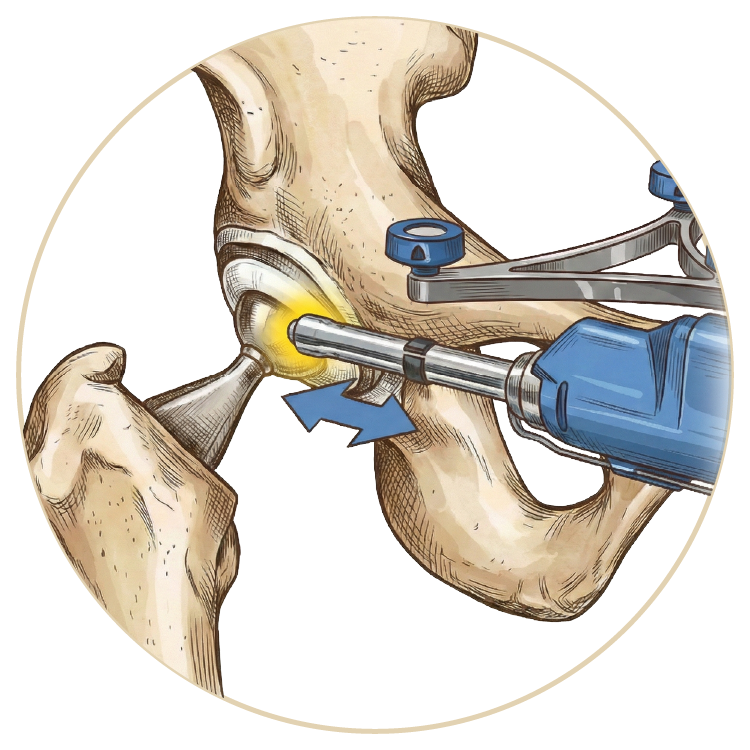

Kalça Hastalıkları ve Tedavileri

Kalça Hastalıkları ve Tedavileri

Kalça Protezi

Robotik Kalça Protezi